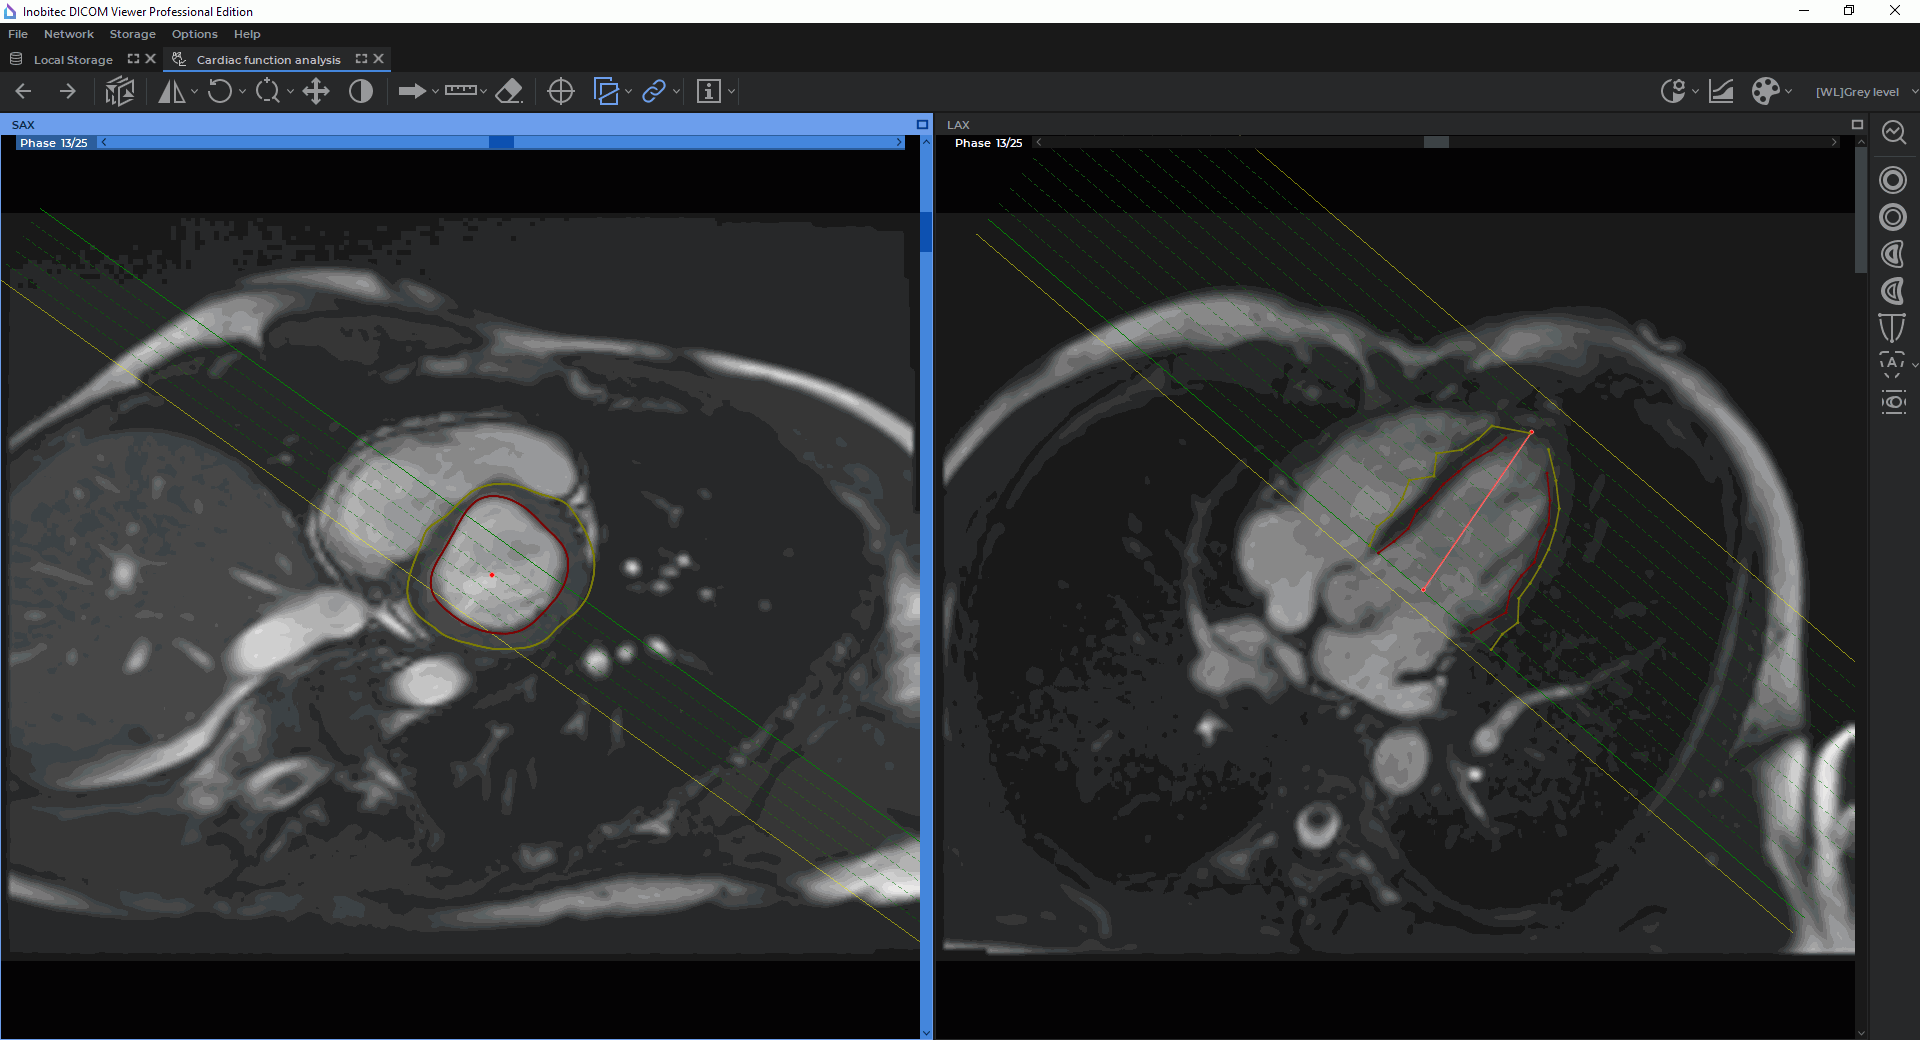

In the Cardiac analysis tab, you can see two windows, with the SAX merged series and the LAX merged series (Fig. 8.2). The toolbar for cardiac function analysis is on the right-hand side of the tab.

| The Endocardial LV contour button is aimed for building and editing the inner contour of the left ventricle manually (the contour is shown in red) |

| The Epicardial LV contour button is aimed for building and editing the outer contour of the left ventricle manually (the contour is shown in yellow) |

The functional parameters of the left and the right ventricles are calculated on the basis of the contours built. Contours can be built separately for each slice and phase in the window with the SAX merged series. The contour boundaries are shown as points on the slices in the window with the merge LAX series. If two or more contours were built for one phase, the points can be connected by segments. You cannot build contours in the window with a LAX merged series.

Automatic contouring of the left ventricle endocardium and epicardium are performed in the window with the SAX merged series for all the phases with the left ventricle extension and all the slices within the extension. The contour boundaries are shown on the slices in the window with the LAX merged series (Fig. 8.6).

Automatic contouring of the left ventricle endocardium and epicardium is performed in the window with the SAX merged series for all the phases. The contour boundaries are shown on the slices in the window with the LAX merged series (Fig. 8.6).